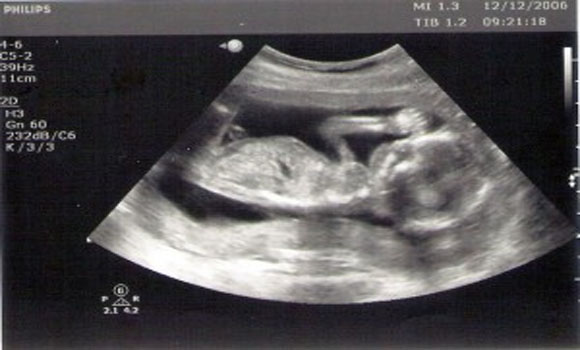

If you had to guess – what would you say is one of the worst things you could do to a developing fetus? Smoking cigarettes? Drinking alcohol? Heavy lifting? Falling down a flight of stairs? Sure – these are all dangerous things to do while pregnant, but another thing that you may not have considered that is actually dangerous to a developing child – ultrasounds!

What do ultrasounds do? Boiled down, they do little more than inform parents about their child’s development and rarely lead to any meaningful action. The only time an ultrasound is actually required is when safety of the child (or mother) is clearly in question and when the results of the test would require action.

- Avoid tests that simply provide information. For example, avoid ultrasounds during pregnancy.